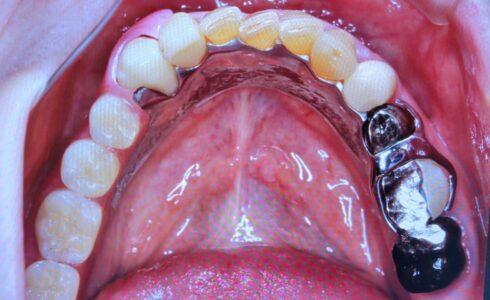

ジルコニア FMZのロングスパンBrの症例です 患者様のご希望でA-1のシェードでの製作でした 2021.05.07 FMZのロングスパンBrの症例です 患者様のご希望でA-1のシェードでの製作でした FMZですので、ステインのみです Tweet シェア 下顎567ジルコニアブリッジ Kdentalでは口腔内スキャナー技工依頼を受付中で...